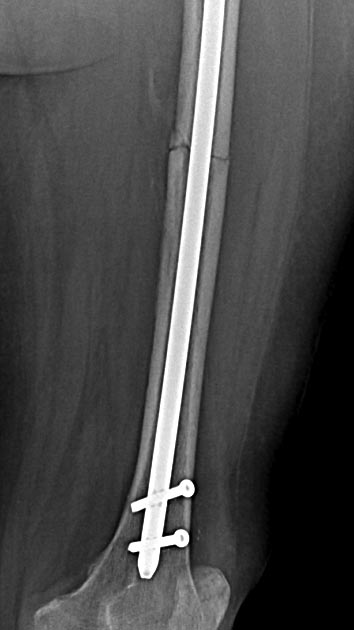

Две несросшихся шейки бедра, пацинтка 27 лет, травме 5 месяцев

БИОС плеча, Чкдо на л/запястный сустав, Биос левого бедра, Мос правой шейки бедра винтами.

Причина обращения -выявленный ложный сустав шейки левого бедра. При дообследовании выявлен несросшийся перелом шейки бедра на винтах.

Опороспособность обеих н/конечностей резко снижена, может стоять на правой, передвигается на каляске.Что думаем: слева однозначно протез, но бедро не срослось, менять гвоздь на пластину, пластина или которкая, или опасность конфликта с ножкой протеза, можно подождать консолидации и разбираться с правой конечностью.Справа остесинтез с коррегирующей остеотомией, но смущает состояние верхнего полюса после миграции винтов, что может повлечь протезирование на фоне нарушения анатомии проксимального бедра, что не хорошо для выживаемости протеза у 27 летней пациентки. Может сразу протез ?КТ головки не информативна из-за винтов